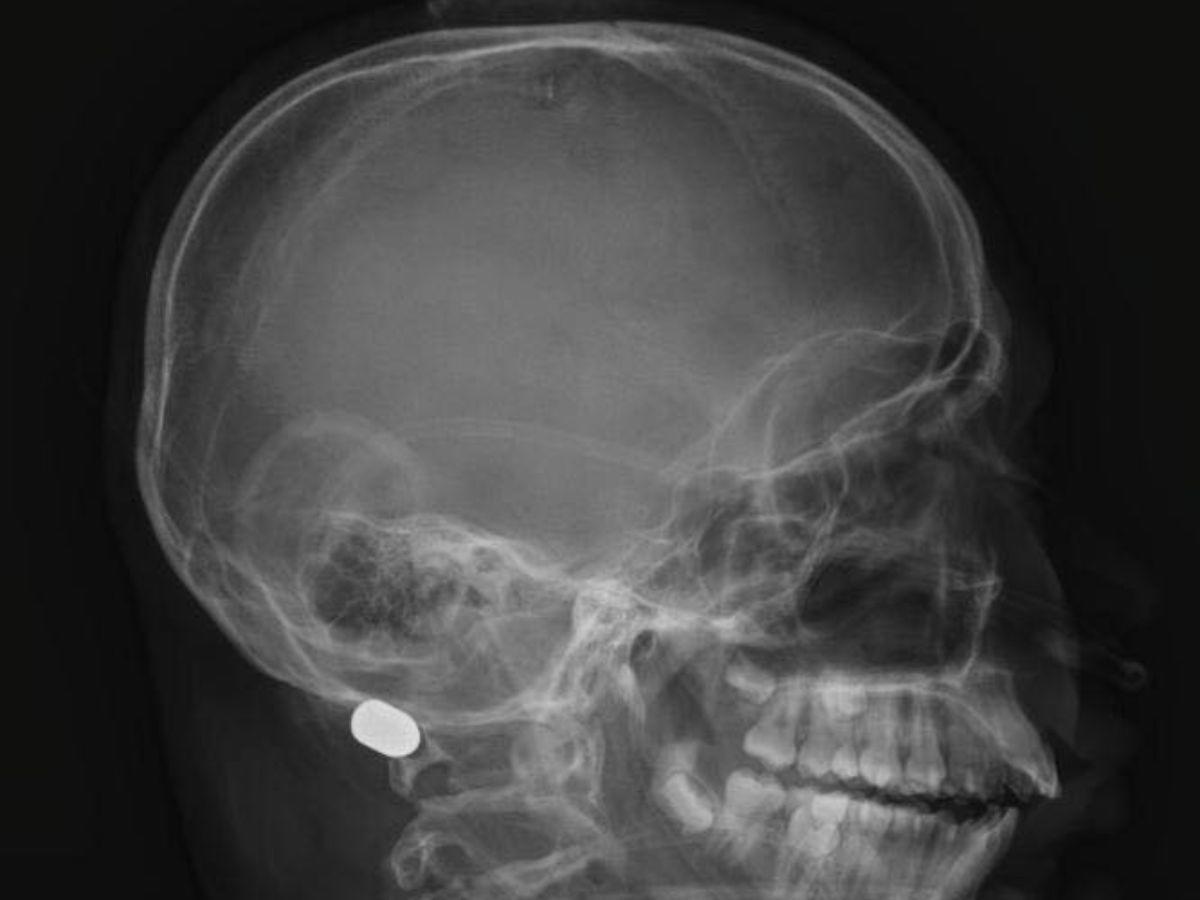

Lamentablemente, Emerson no logró sobrevivir. Radiografías muestran que la bala impactó entre la médula espinal y el cerebro, acabando así con su vida.